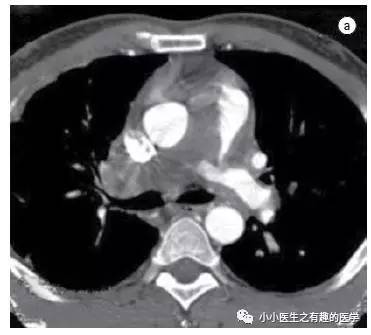

文献3:足球王国巴西报道的一例。

这是什么?

病理:Intimal sarcoma of the pulmonary artery:肺动脉内膜肉瘤。

仔细看看:

CT示肺动脉内肿块,肿块侵犯纵膈,血栓不会跑到纵膈。